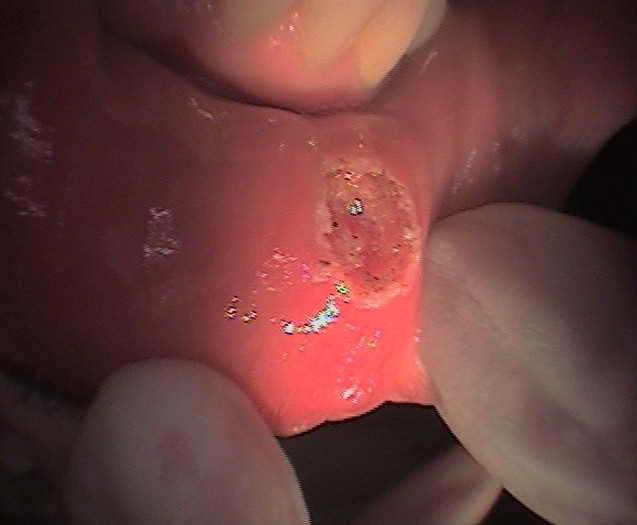

Fibroma Removal Before